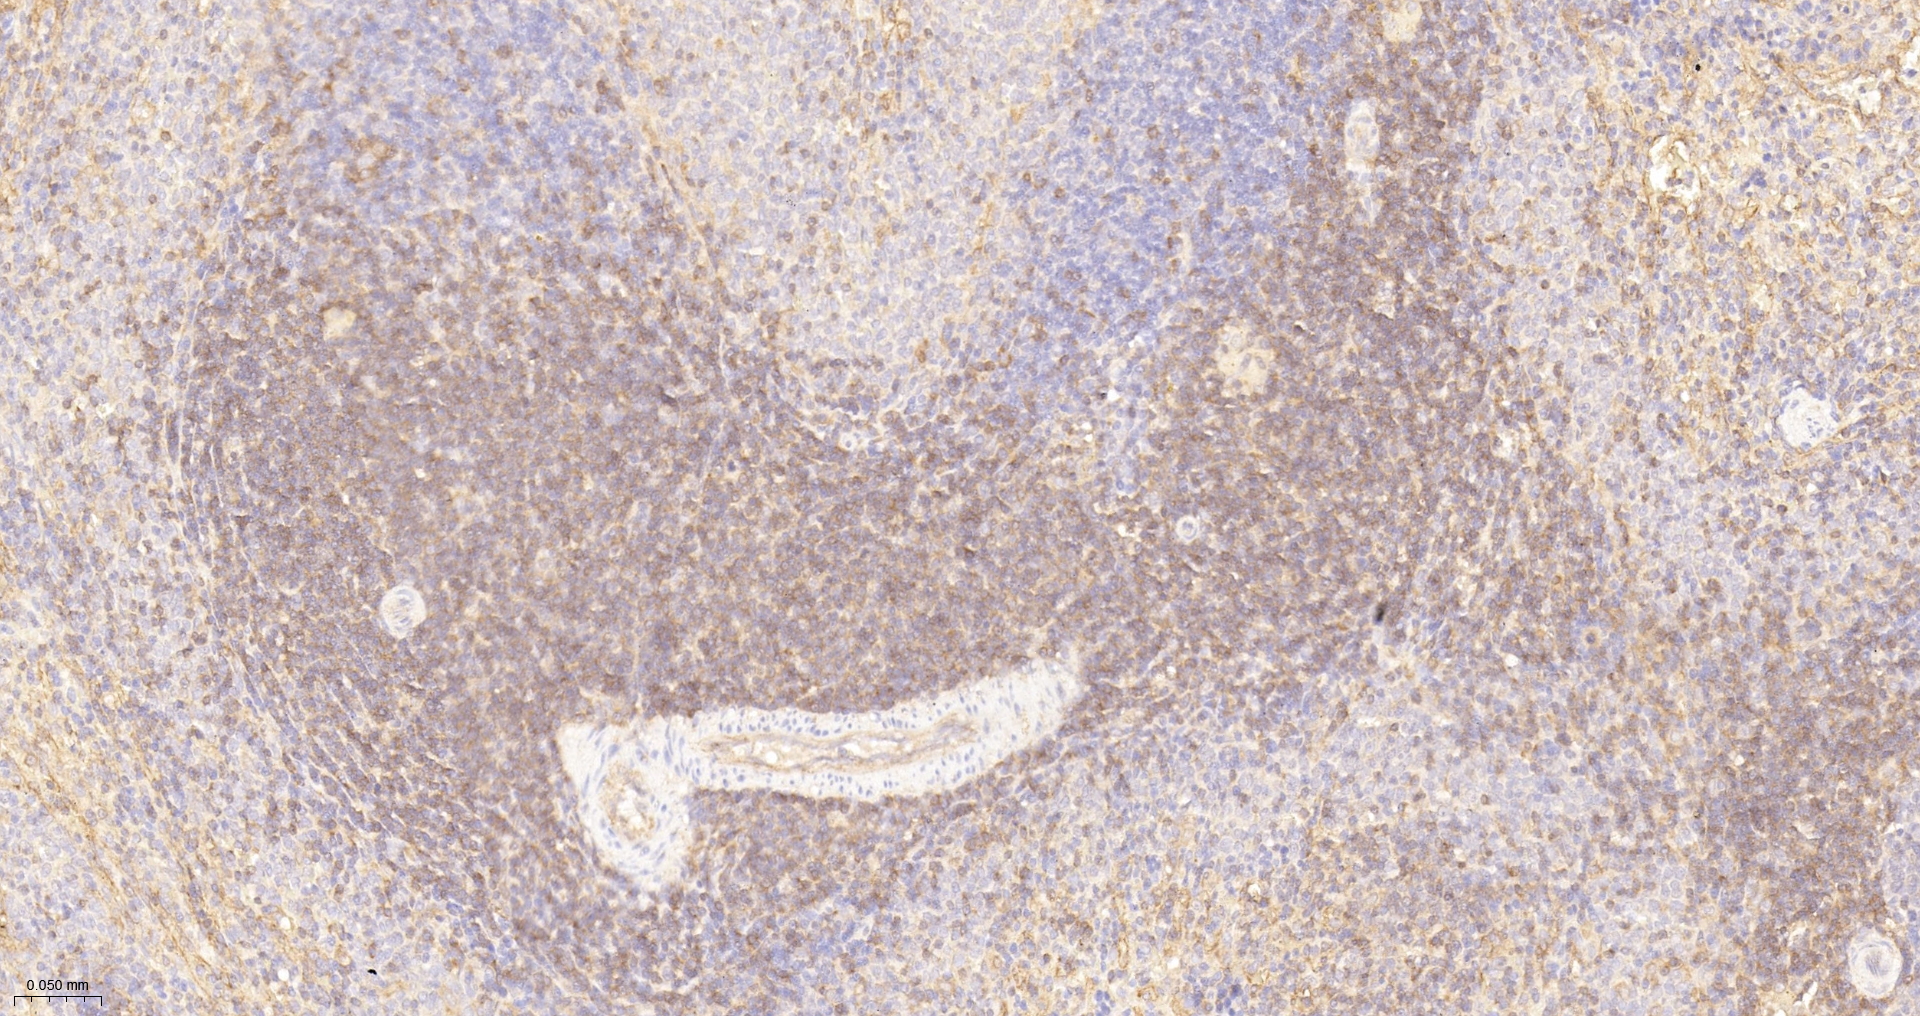

• IHC-P

IHC-P IHC-P1:100-500